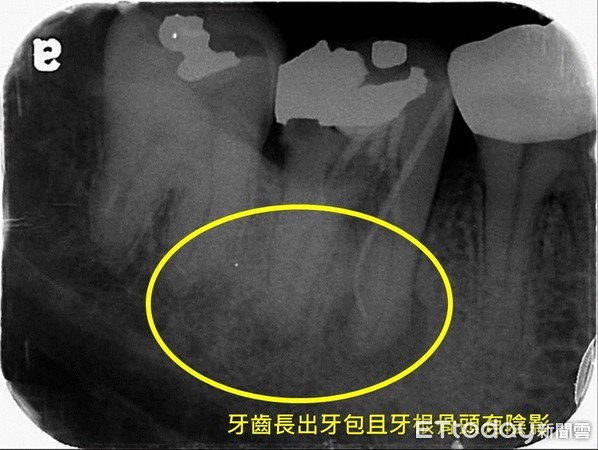

郭祉吟医师问诊检查后,发现患者牙齿已经抽过神经,但牙齿神经管内还有残余的细菌,且牙齿再蛀牙、没有做很好的填补,造成细菌跟着口水再跑进神经管,进而扩散到牙根外的颚骨,细菌再沿着颚骨侵蚀到外面的牙龈,就会长出产生俗称的「牙包」,X光片上显示牙根有阴影,确诊为牙根脓肿,必须要做「根管治疗」。

大部分病人都认为,已经抽过神经就再也不需要抽神经也不会再有问题了。其实抽神经只是一个通俗的说法,正式名称是「根管治疗」。牙齿根管是牙齿中一个软组织的管道,连接牙齿内部跟牙根外部颚骨里的神经血管系统,因此在牙齿根管中不只有神经而已,还有血管及其他组织,一个成功的根管治疗不只是把神经抽掉而已,同时还要把管道内部做彻底的消毒,让细菌量减到最低,甚至到无菌状态。更重要的还是要确保牙齿蛀牙和治疗开口有紧密的封填,也就是管道开口的密封性要够好,否则根管内的残余细菌沿着向下孳生到牙根底部往骨头扩散,就会开始侵蚀牙根周围的骨头,而在X光检查下会发现牙根出现一圈黑影。